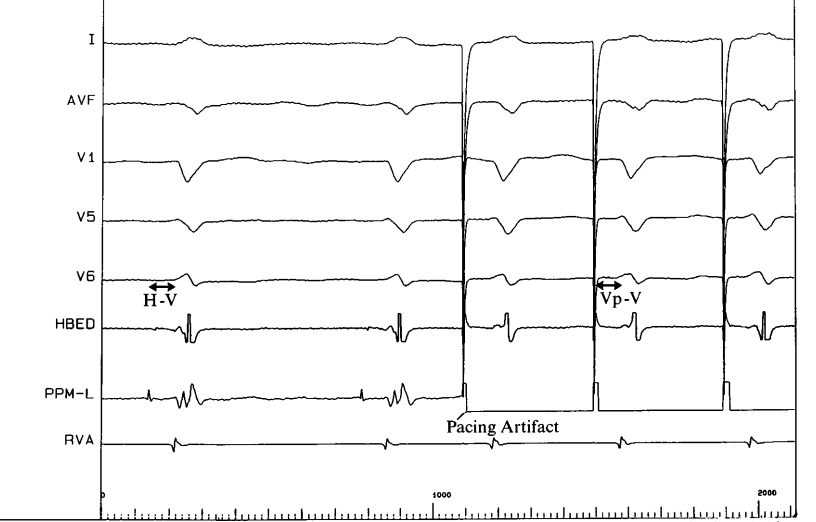

deshmukh_pacing.png

Deshmukh P, Casavant DA, Romanyshyn M, Anderson K. Permanent, direct His-bundle pacing: a novel approach to cardiac pacing in patients with normal His-Purkinje activation. Circulation. 2000 Feb 29;101(8):869-77.